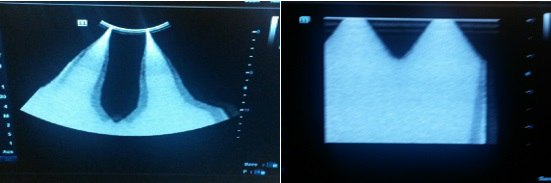

⚠️ Проблема: После включения прибора DC-70 на экране иногда появляются две белые полосы, как показано на рисунках ниже. После перезагрузки полосы исчезают.

💡 Причина: Программируемая логическая матрица TR-FPGA на плате TR64 вышла из строя, что приводит к соответствующему сбою.

✅ Решение: Программируемая логическая матрица TR-FPGA на плате TR64 в аппарате Mindray DC-70 была изменена на ECN (EGD019F). При столкновении с такой проблемой на DC-70, обновите программное обеспечение Doppler до версии V01 08 01 или выше.